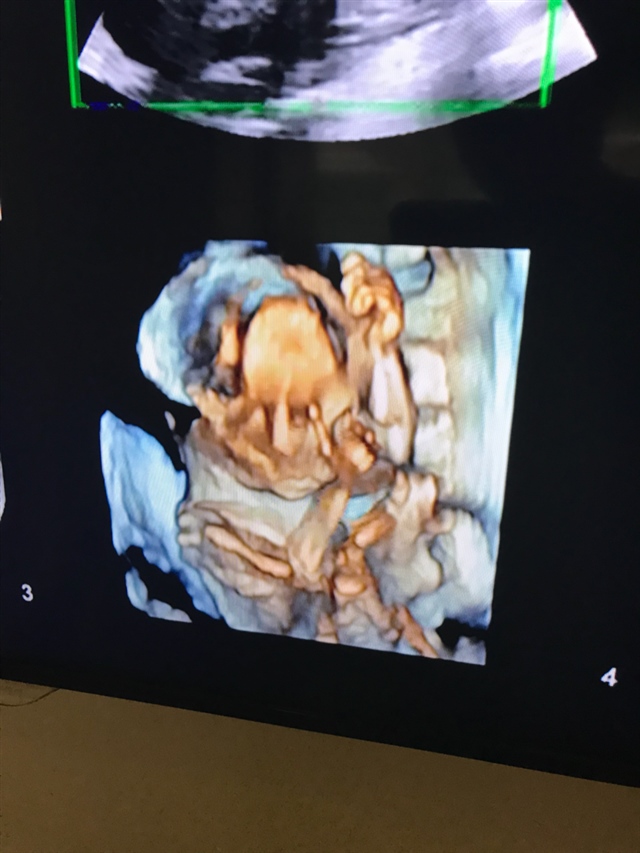

这是几维,画质看着有点恐怖